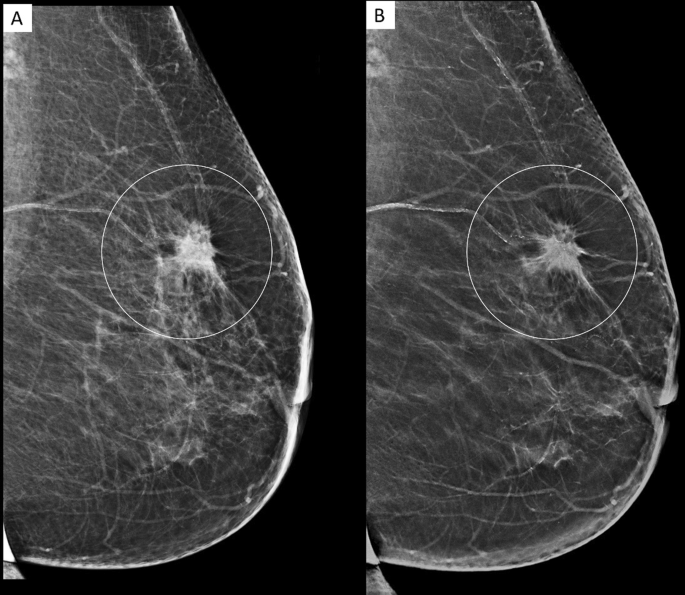

Digital tomosynthesis image This picture demonstrates digital tomosynthesis.